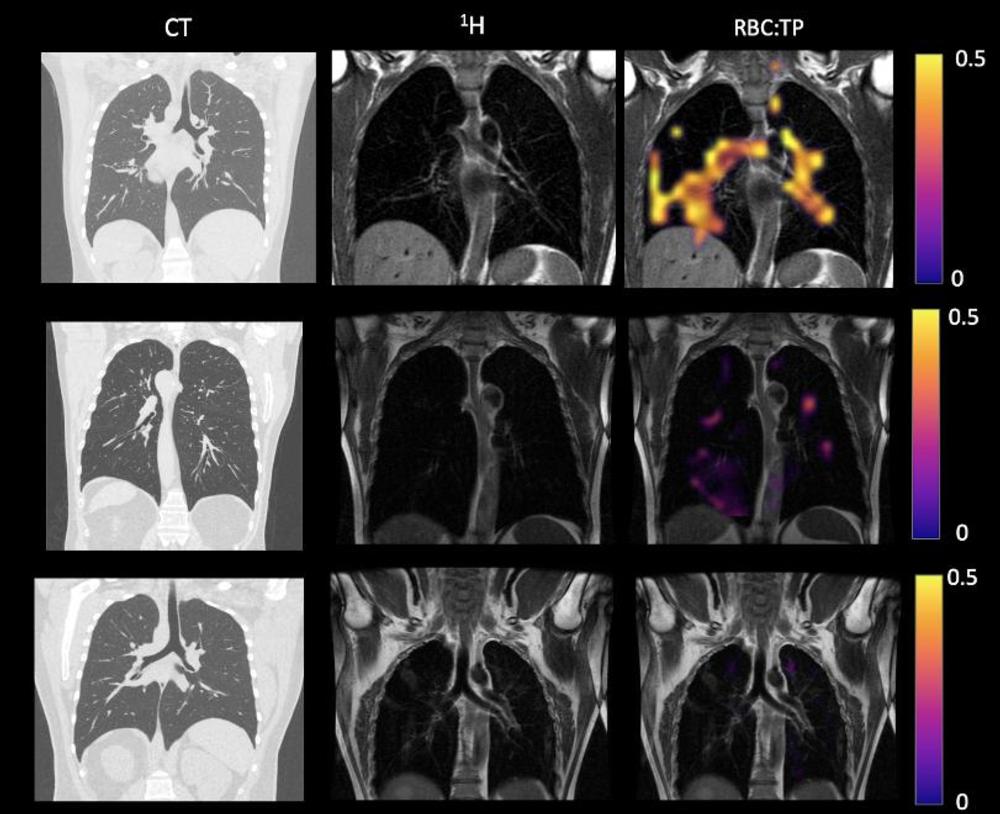

Figure 3. Example CT, proton, proton and RBC:TP imaging from post-hospitalized participants. The top row is a participant with RBC:TP = 0.59, the middle row is a participant with RBC:TP of 0.31, and the bottom row is a participant with RBC:TP = 0.16. Imaging showed minimal damage on CT, and yet highly heterogeneous and low RBC:TP in the lungs of post-hospitalized participants. RBC:TP = Hyperpolarized 129Xenon MRI lung ratio of red blood cell spectral peak to tissue phase spectral peak

High-res (TIF) version